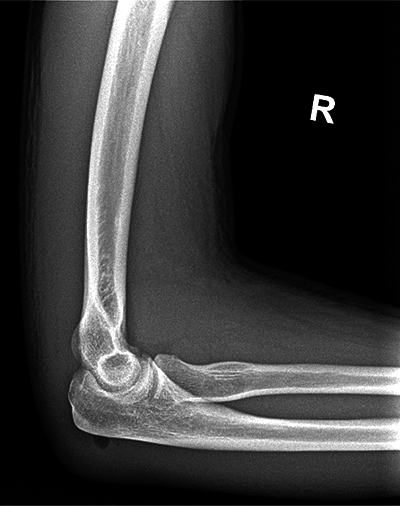

教学要点:强调在肌肉骨骼超声中识别镜像伪影的重要性,以避免误诊、不必要的干预和额外的诊断程序,从而导致患者焦虑、医疗费用增加和潜在的伤害。

Teaching point: To emphasize the importance of recognizing mirror image artifacts in musculoskeletal ultrasound to avoid misdiagnosis, unnecessary interventions, and additional diagnostic procedures that can lead to patient anxiety, increased healthcare costs, and potential harm.